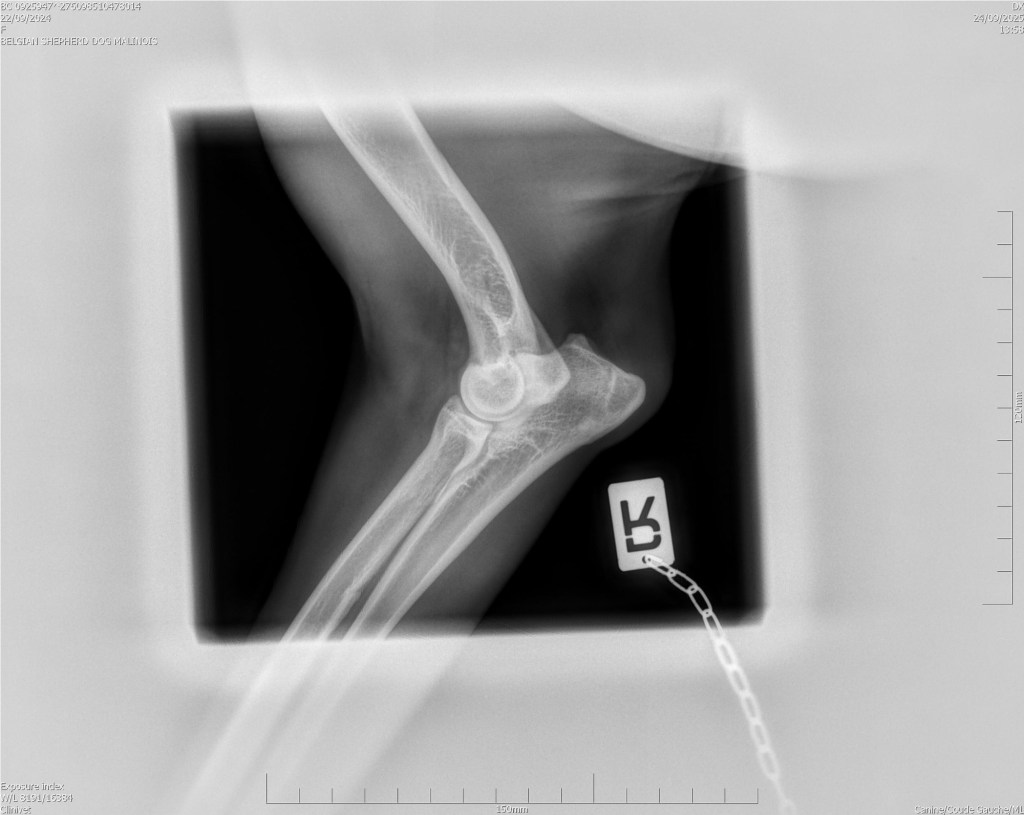

Hips 2/3

Elbows 0/0